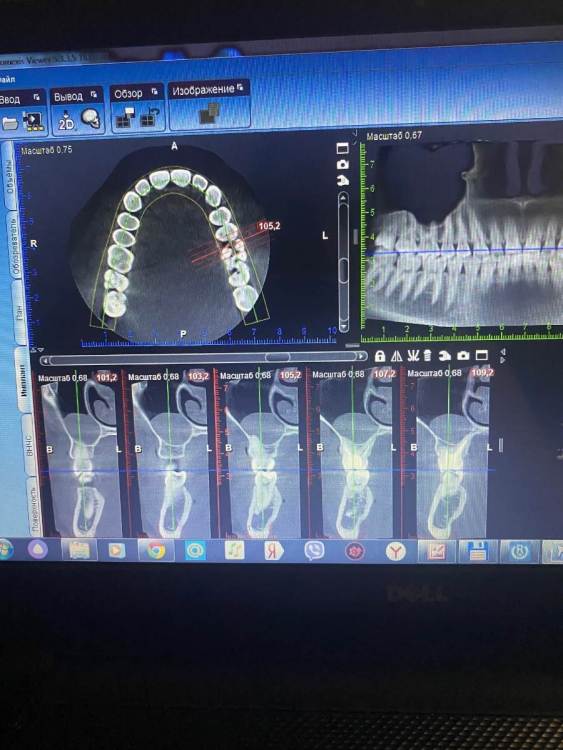

АлинаЯга Опубликовано 14 июня, 2022 Автор Поделиться Опубликовано 14 июня, 2022 @red_butler сделала сегодня кт . Киста такая огромная? Ссылка на комментарий